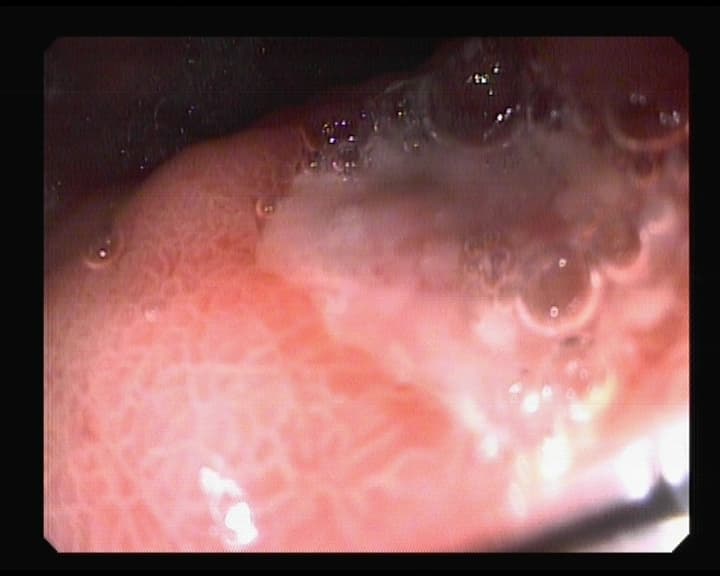

Punto sangrante anterior foto, ya solucionado.

Resultado del punto sangrante en duodeno ya tratado.